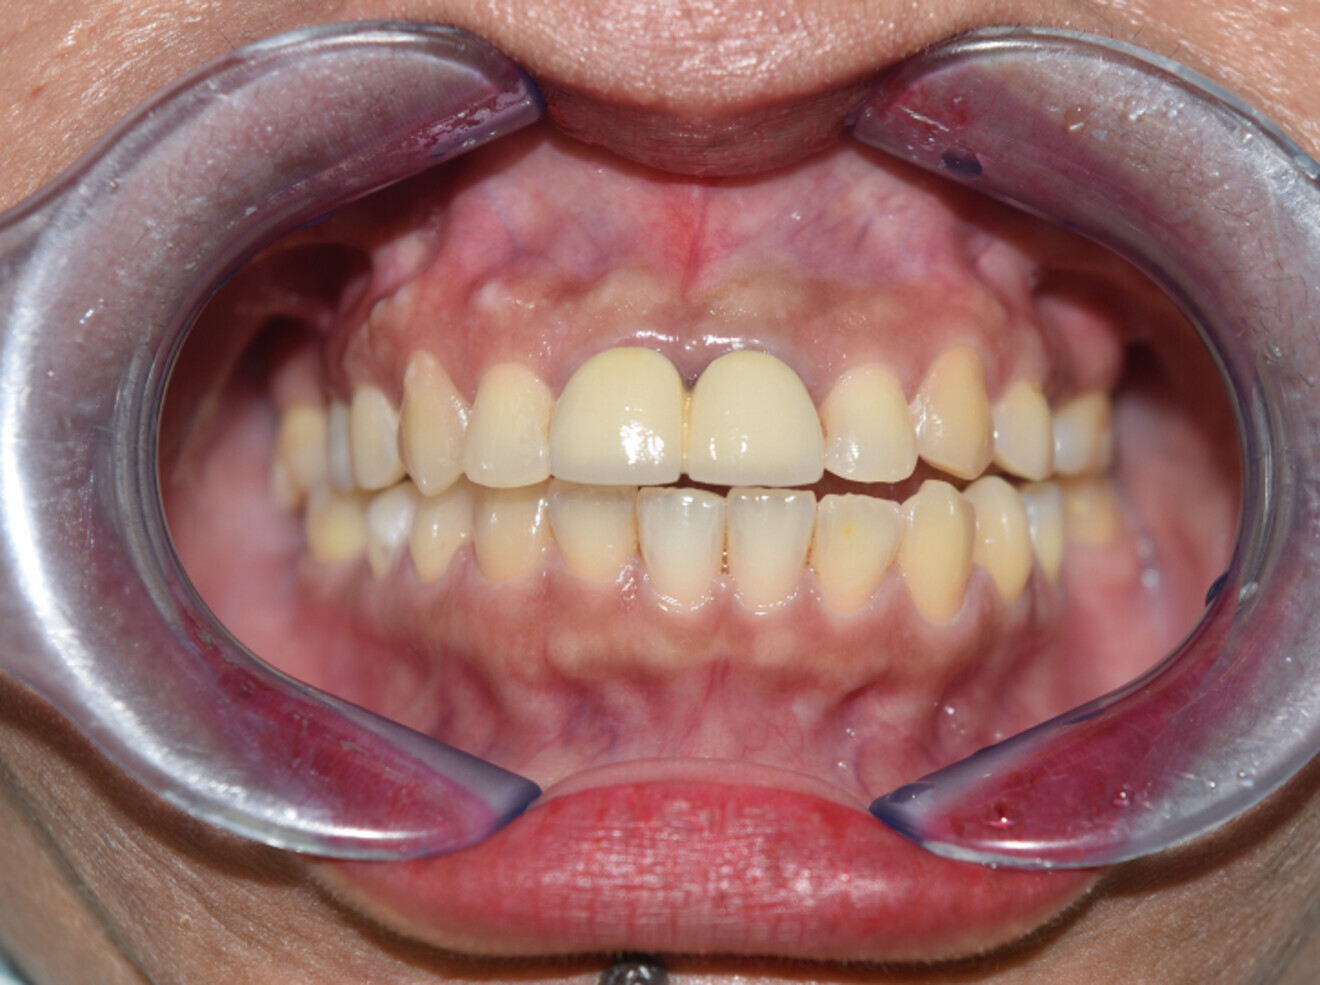

Fig. 13b: 2 years post ortho dontic treatment.

Fig. 13c: 4 years post orthodontic treatment.

Fig. 14a: After debond.

Fig. 14b: 2 years later.